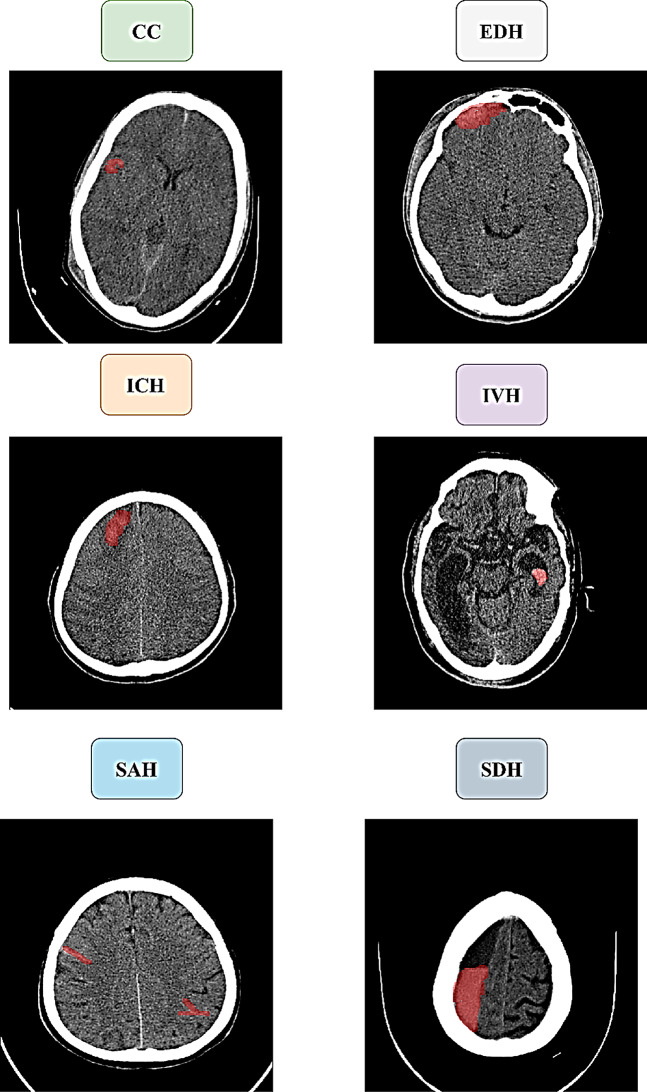

Materials and methods: A dataset of 1,347 patient CT scans was collected retrospectively, covering six types of hemorrhages: subarachnoid hemorrhage (SAH, 231 cases), subdural hematoma (SDH, 198 cases), epidural hematoma (EDH, 236 cases), cerebral contusion (CC, 230 cases), intraventricular hemorrhage (IVH, 188 cases), and intracerebral hemorrhage (ICH, 264 cases). The dataset was divided into 80% for training using a 10-fold cross-validation approach and 20% for testing. All CT scans were standardized to a common anatomical space, and intensity normalization was applied for uniformity. The ResUNet model included attention mechanisms to enhance focus on important features and residual connections to support stable learning and efficient gradient flow. Model performance was assessed using the Dice Similarity Coefficient (DSC), Intersection over Union (IoU), and directed Hausdorff distance (dHD).

Results: The ResUNet model showed excellent performance during both training and testing. On training data, the model achieved DSC scores of 95 ± 1.2 for SAH, 94 ± 1.4 for SDH, 93 ± 1.5 for EDH, 91 ± 1.4 for CC, 89 ± 1.6 for IVH, and 93 ± 2.4 for ICH. IoU values ranged from 88 to 93, with dHD between 2.1- and 2.7-mm. Testing results confirmed strong generalization, with DSC scores of 93 for SAH, 93 for SDH, 92 for EDH, 90 for CC, 88 for IVH, and 92 for ICH. IoU values were also high, indicating precise segmentation and minimal boundary errors.